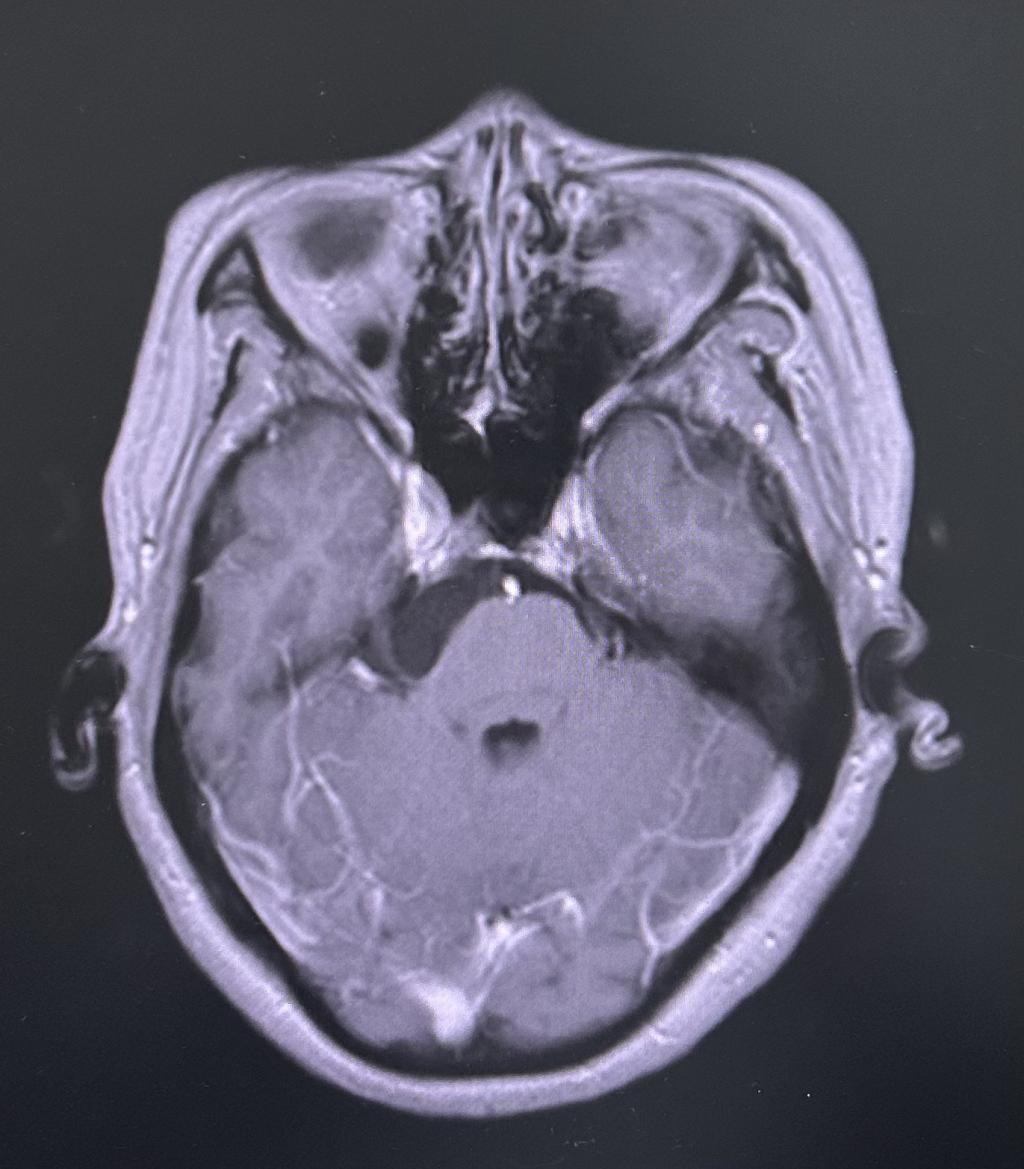

为求进一步治疗,贾女士慕名来到我院门诊就诊。门诊行颅神经-平扫(MR)提示:右侧桥小脑角区占位性病变,收治入神经外科住院治疗。

患者术前核磁共振影像